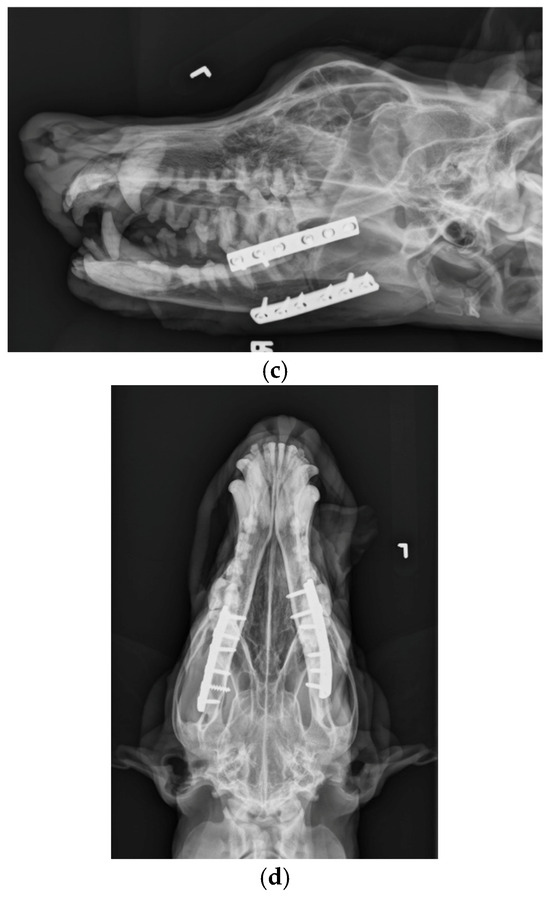

A 6-hole, 3.5 mm compression plate was placed on the lateral aspect of each mandibular body.

Figure 6.

(a). Lateral. (b). Right dorsal-left ventral oblique. (c). Left dorsal-right ventral oblique. (d). Ventrodorsal view demonstrating bone plates and screws applied to the mandibular ramus bilaterally.

The patient was placed in dorsal recumbency and aseptically prepped from the level of the second tracheal ring to the rostral mandible and laterally to the ventral border of the zygomatic arch. An incision was made bilaterally over the caudal two-thirds of the ventral border of the mandibles and through the platysma muscle for exposure of the periosteum. The myloglossus and digastricus muscles were elevated from their attachments on the bone. A bilateral mandibular wedge ostectomy was performed, and bone plates and screws were used on either side to stabilize the mandibles to allow the mouth to remain permanently open to allow drinking, eating, and panting. (Figure 4 and Figure 5). The proposed ostectomy was outlined on the lateral and medial surfaces of each mandible. An oscillating bone saw was used to perform osteotomies along the medial and lateral aspects of each mandible, avoiding the mandibular canal. An osteotome was used to separate any remaining attachments between bones. The oral opening was visualized by a nonsterile assistant, and a spacer was placed to maintain an opening of approximately 3.5 cm. Bone was removed with the sagittal saw to create a closing wedge ostectomy to maintain the desired oral opening and maintain cortical contact of the mandible. Six-hole, 3.5 mm dynamic compression plates were placed on the ventrolateral aspect of the right and left mandibles with self-tapping, cortical screws to oppose the ostectomy sites, taking care to avoid tooth roots. Cancellous bone from the removed bone wedges was placed at the ostectomy lines. A minor operative complication was left mandibular artery trauma with hemorrhage that was controlled with bone wax. The post-operative radiographs confirmed both reduction and stabilization of the mandibular ramus bilaterally by means of the two plates. The tooth roots were avoided with screw placement (Figure 5 and Figure 6). The 3.5 cm opening was maintained between the upper and lower incisors postoperatively (Figure 7).